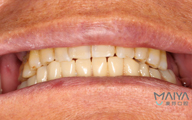

我种牙后并没有什么不适,下牙的牙齿种好了,我又找麦芽的硕博专家把上牙的几颗牙齿也种了,绝对不能因为一颗坏牙再引发其他的口腔问题。临时牙冠佩戴没有任何不适,做了永久修复,而且麦芽的硕博专家还给我分析下牙和上牙的咬合关系,不能随便就戴牙冠,种的好是一方面,更重要的是咬合和使用功能。

这两年陆续去麦芽复诊,医生看完我的牙齿说维护的很好,需要坚持下去,不能因为种完牙就对它不管不顾,按时刷牙和用牙线清洁,据说我的种植牙维护的好可以用上好几十年,每天成本顶多才6毛钱,跟之前的假牙相比又美观,又舒服。